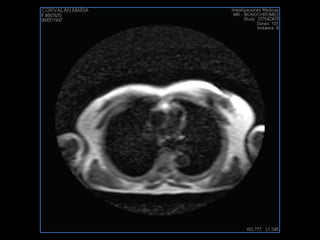

PROTOCOLO pelvis SAG T2, Y FAT SAT (FINOS) AXIAL T1  AX FAT SAT CON   GADOLINIO :  AX T1 Y COR T1 SAT: NO  FASE: RL THK: 3MM  COIL:  GAP: (FACTOR 1.4) 1MM FOV: 40 CM NEX:2 SINCRONIZACION RESPIRATORIA EN 3 O 4 CICLOS ALE